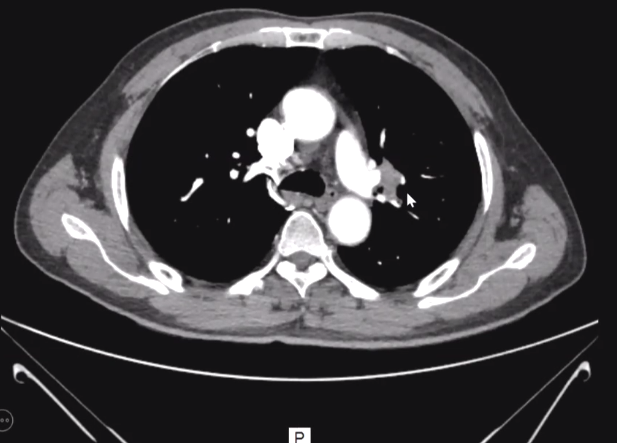

于2020-05-17“间断咳嗽、痰中带血20余天”入院。

2020-05-19左肺上叶尖后段开口狭窄近乎闭塞,活检为鳞癌Bbw帝国网站管理系统

经MDT讨论,行帕博利珠单抗紫杉醇顺铂(新辅助治疗2周期)。Bbw帝国网站管理系统

新辅助治疗后行手术治疗。送检左上叶肺为后段肺癌(非角化型鳞癌,0.8X0.5X0.2cm大小),间质伴纤维结缔组织增生及炎性肉芽组织增生。余肺淤血,气肿,部分区域纤维结缔组织增生伴瘢痕形成。送检(左肺上叶支气管残端)未见癌侵及。标本血管断端未见病侵及。

新辅助免疫治疗中,比起腺癌患者,鳞癌患者往往更容易获益。经过新辅助治疗后的手术核心难度明显降低。免疫所带来的缓解与化疗带来的缓解不同。至于最佳手术时机,仍需更多进一步探索。Bbw帝国网站管理系统

Bbw帝国网站管理系统

免疫治疗通过激活人体自身对抗肿瘤的免疫功能来杀死肿瘤细胞。新辅助免疫治疗在目前研究中尚未增加手术难度,且提升疗效,患者也从中得到更多获益。与所有免疫治疗一样,新辅助免疫治疗的不良反应仍需关注。Bbw帝国网站管理系统